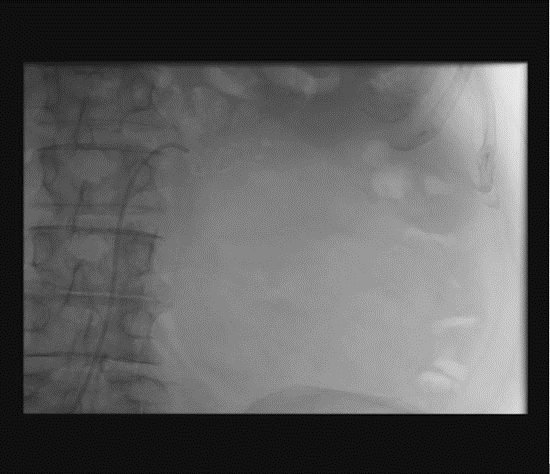

Renal artery embolization was performed under local anesthesia using the Seldinger technique, with complete occlusion confirmed angiographically (Figures 3-4). Six days later, a transabdominal left radical nephrectomy was performed. Intraoperatively, the kidney appeared markedly enlarged and deformed, containing cystic and soft-tissue components but without invasion of adjacent structures (Figures 5-6). The operation was uneventful, with minimal blood loss (approximately 300 mL) and no transfusion requirement. The postoperative course was smooth, and the patient was discharged on postoperative day five in good condition. Histopathological examination revealed that the upper pole lesion corresponded to a low-grade clear cell RCC with focal necrosis (Figures 7-8). The larger lesion was identified as a well-differentiated liposarcoma (Figures 9-10), correcting the initial radiologic misdiagnosis of angiomyolipoma. At the three-month follow-up, the patient remained asymptomatic. Laboratory results indicated mild renal impairment (creatinine 169 µmol/L, urea 9.2 mmol/L) but normal inflammatory markers. Ultrasonography revealed no recurrence or lymphadenopathy. Nephrology follow-up was continued due to reduced renal function. Six months postoperatively, CT imaging of the thorax, abdomen, and pelvis demonstrated no evidence of local recurrence or distant metastasis. Given the absence of standardized surveillance protocols for synchronous RCC and WDLPS, followup was conducted in accordance with conventional RCC and retroperitoneal sarcoma guidelines.

Figure 4: Post-embolization angiography showing successful